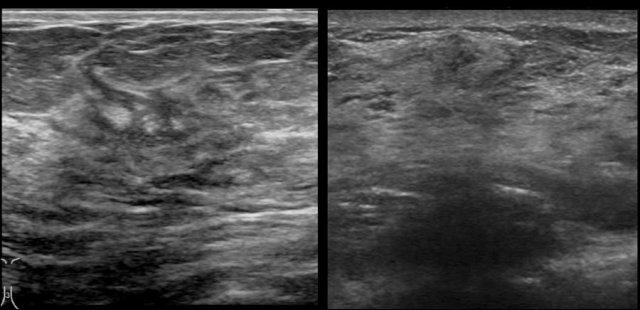

The way that the breasts present on an ultrasound image may differ between machines of different manufacturers.

This means that you have to get used to the images on your own ultrasound machine.

The images are of a Philips (left) and Siemens (right) ultrasound machine.

Look for instance at the difference in the presentation of the skin.